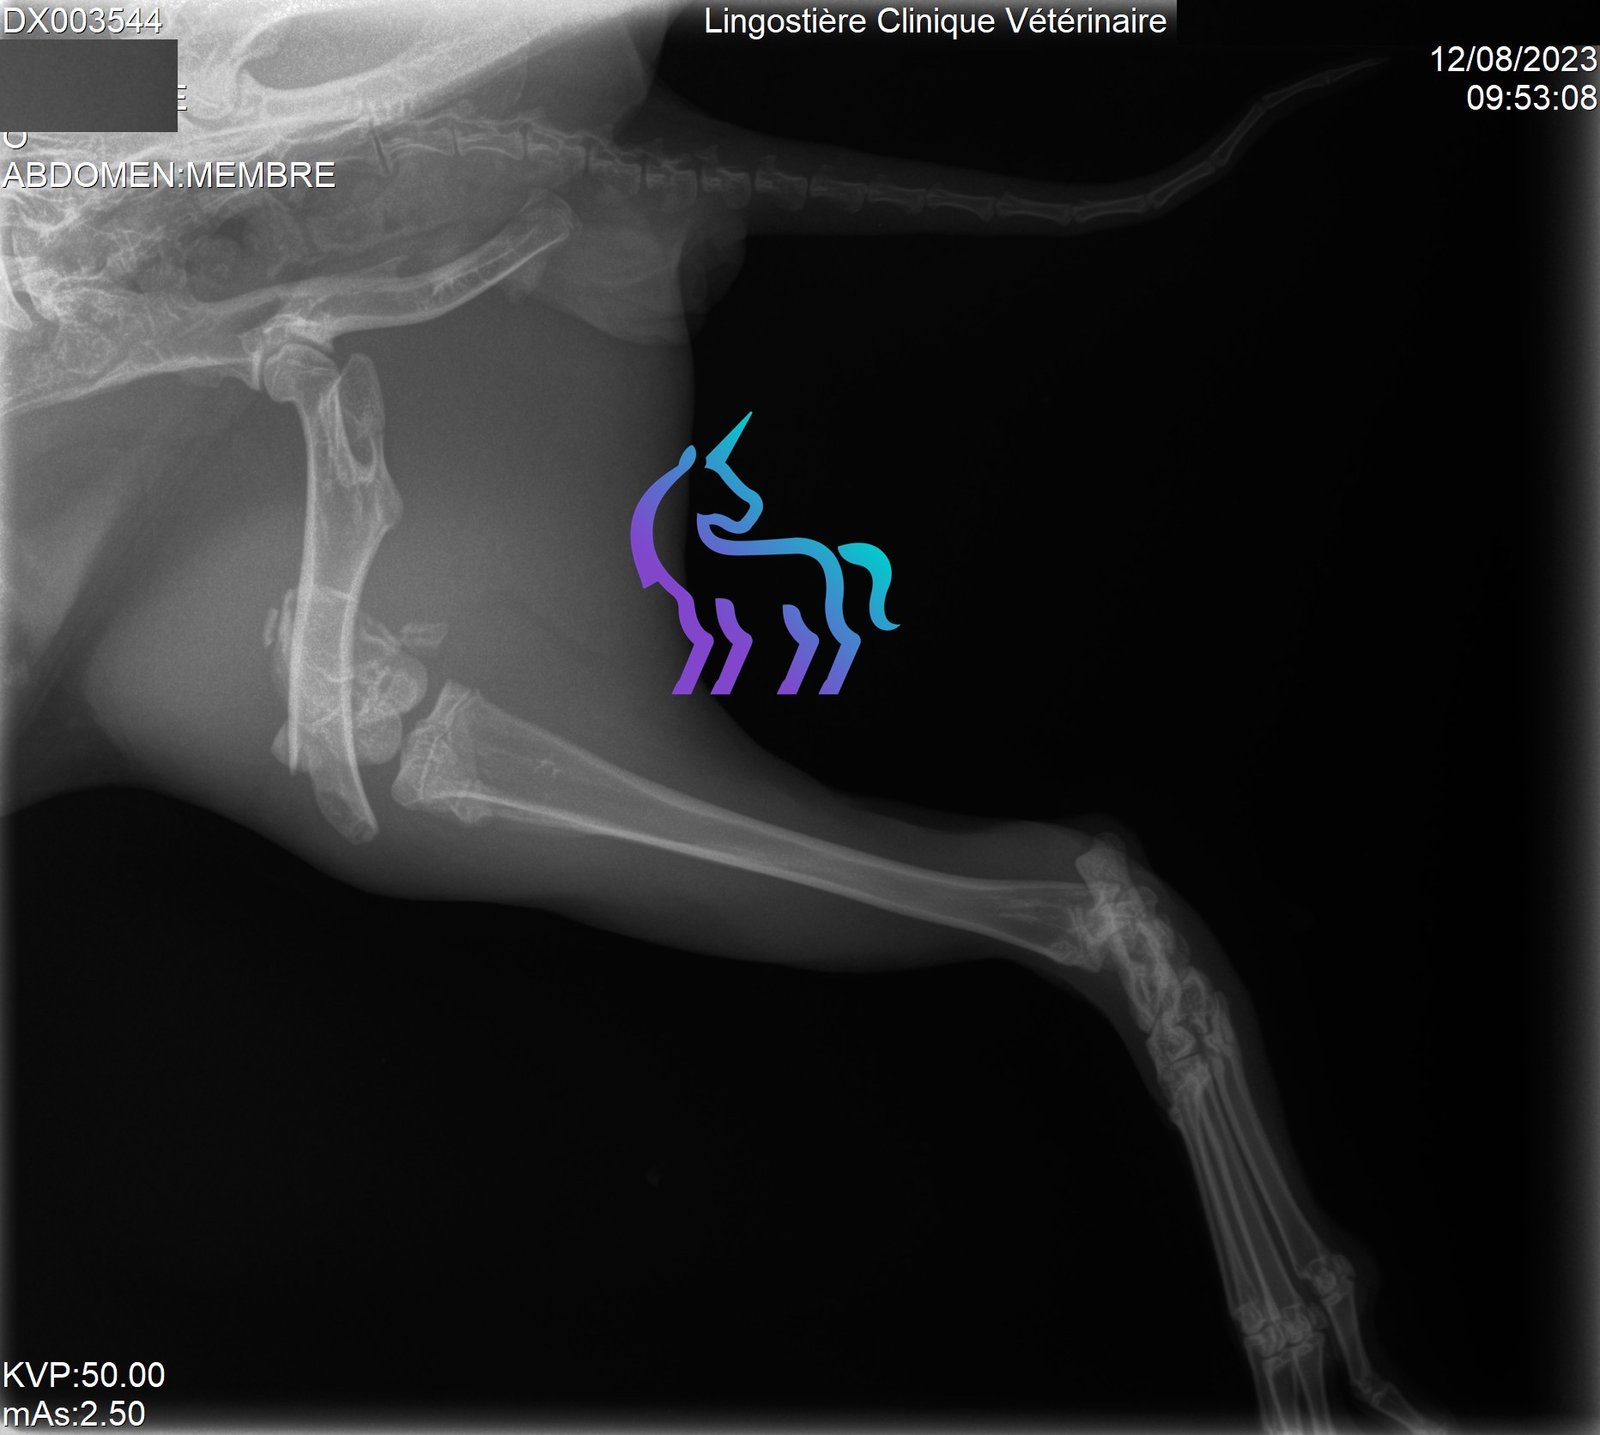

Oui (bassin, membres). Une douleur importante peut entraîner anorexie puis stase digestive.

Quels examens sont utiles ?

Radiographies pour fractures/arthrose, scanner/IRM si suspicion lésion vertébrale.Amputation : dans quels cas ?